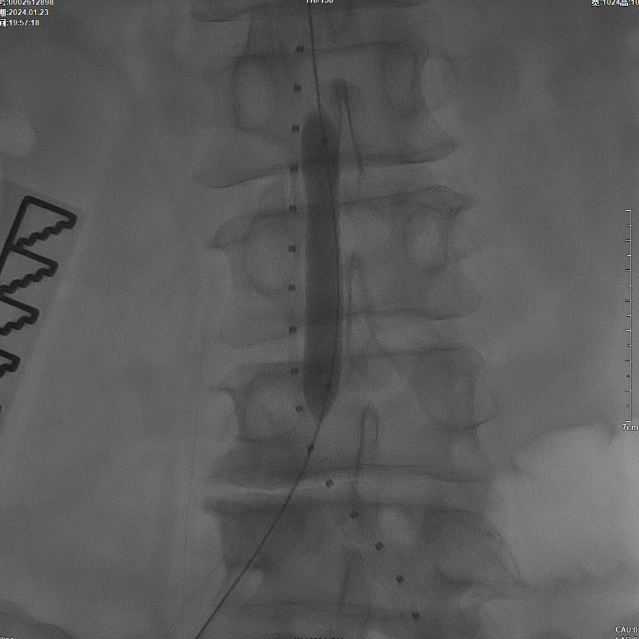

在超声引导下,成功完成双侧股总动脉穿刺。通过导管配合超滑导丝,顺利通过病变区域进入腹主动脉下段,造影明确腹主动脉下段及双侧髂动脉完全闭塞的病变范围与程度。

减容治疗

采用8F Rotarex导管对双侧髂动脉及腹主动脉下段进行减容处理。该器械对于陈旧性血栓具有良好的清除效果,且适用于支架内病变的治疗。减容治疗的主要目的在于获得理想的管腔空间,同时降低远端动脉栓塞的风险。